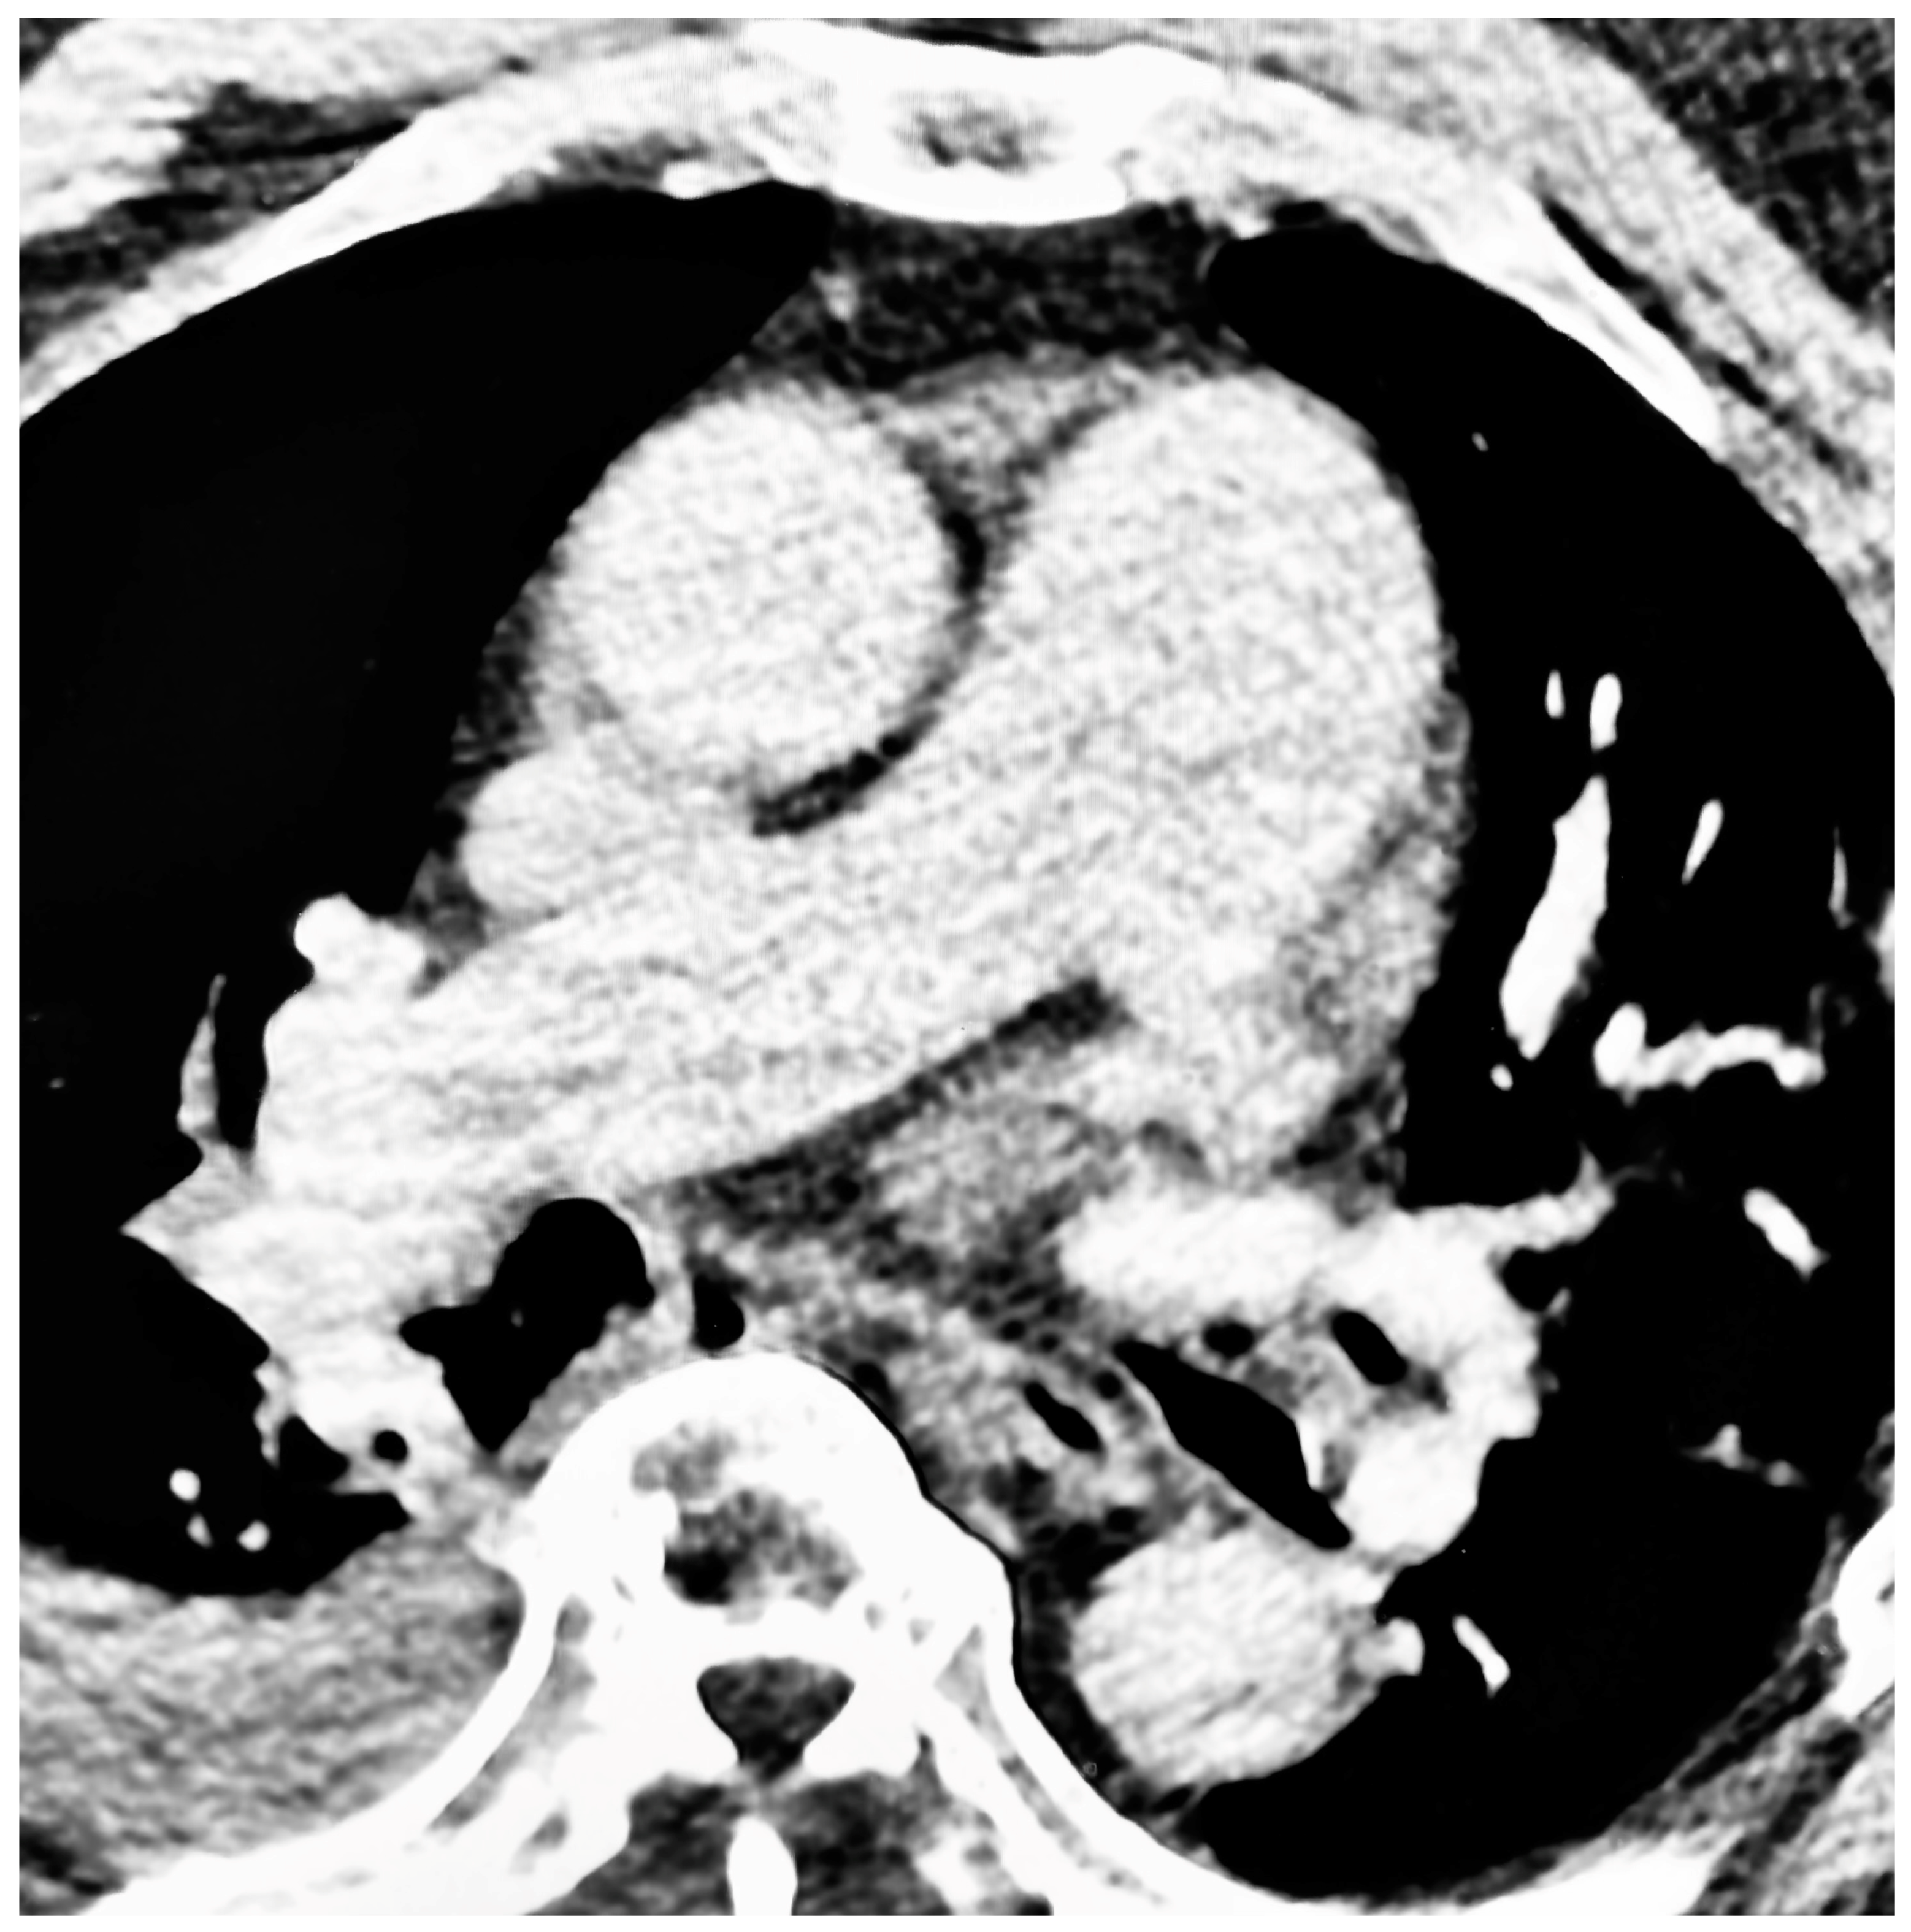

Figure 1.

Pulmonary hypertension in a patient with sleep apnea. Axial, contrast-enhanced CT scan of the thorax with a section taken at the level of the main pulmonary artery bifurcation. The main pulmonary artery has a width of 49 mm. Incidental note is made of a moderate right pleural effusion.